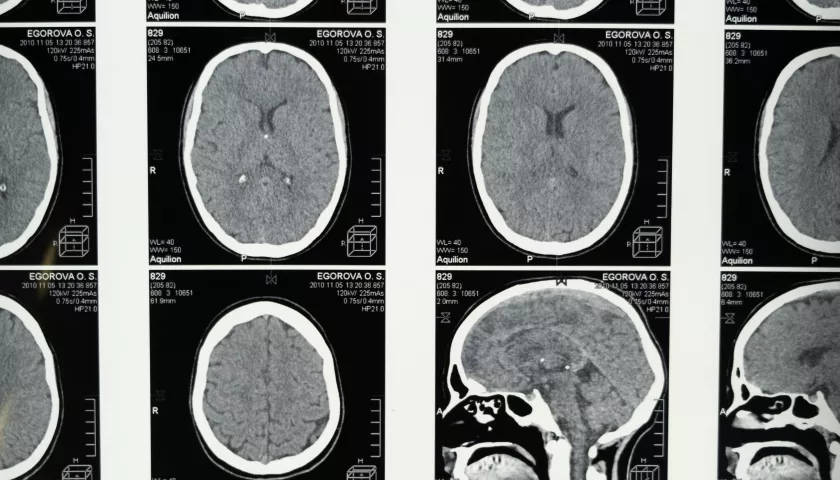

nelle attività formative professionalizzanti nelle diverse articolazioni della Clinica Neurologica e della rete formativa, incluse le attività ambulatoriali e le attività diagnostiche (neurofisiologia, neurosonologia, neuropsicologia, neuroradiologia).